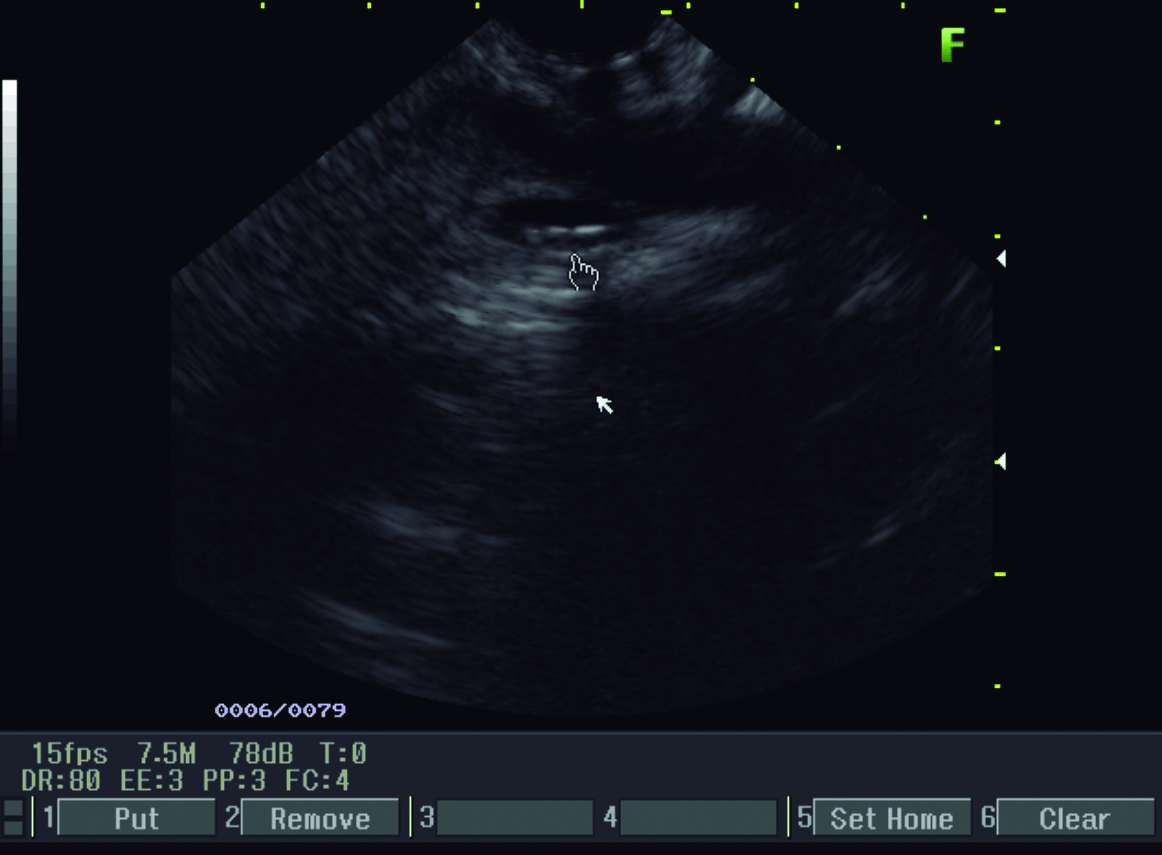

Figura 3. Ecoendosopía

a y b) Líneas hiperecoicas alargadas, paralelas de 3 mm de diámetro compatible con Ascaris (mano).